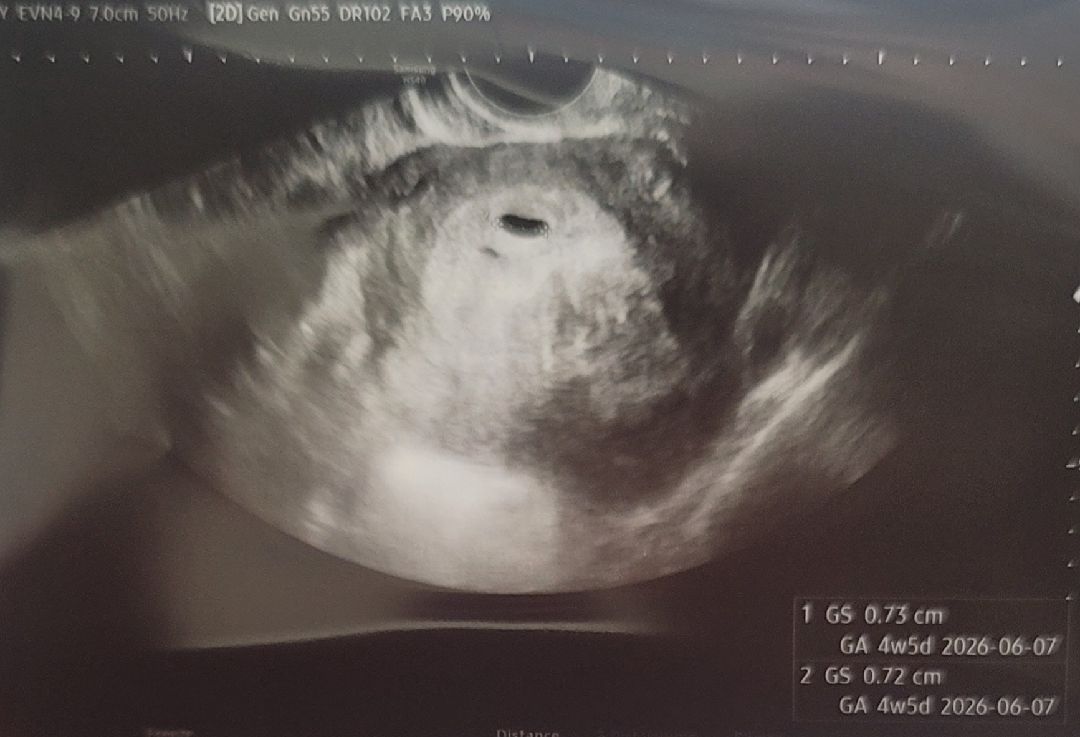

임신은 일주일전에 테스트기로 확인했고 어차피 난황은 5주 3일쯤 지나야 보인다고 해서 6주차에 가보려고 했거든요. 근데 어제 스트레스가 극심해서 잠도 설치고 밤새 심장 두근거리고 식은땀을 너무 흘려서 아침부터 배가 빠지는 느낌이 나서 경련이 오려고해 다리를 오므리기가 힘들더라구요..ㅠ 안되겠다 싶어 내원해서 오늘 아기집 확인하고 왔는데 질초음파로 봤고 0.73라고 하더라구요. 다른건 괜찮은데 초음파하고 난 직후에 피가 주루룩 쏟아져서 덩어리도 있고 짙은 갈색이랑 출혈이 꽤 많이 나와서 걱정이 되더라구요. 혹시 저와같이 난황 보기전에 출혈이 있었던 분이 계실까요? 아기가 자라는데 큰 문제는 없는걸까 걱정이 됩니다. 비슷한 경험이 있으시면 알려주세요ㅠㅠ